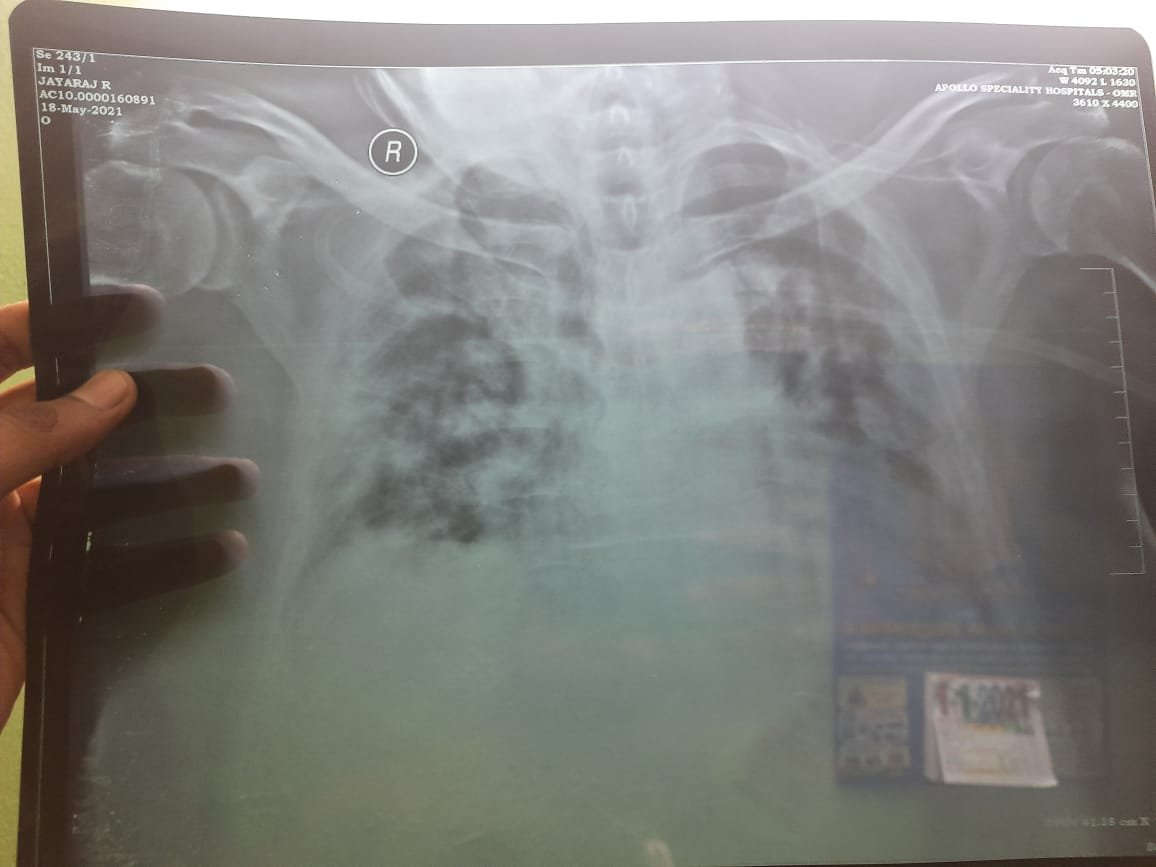

COVID-19 Success Stories